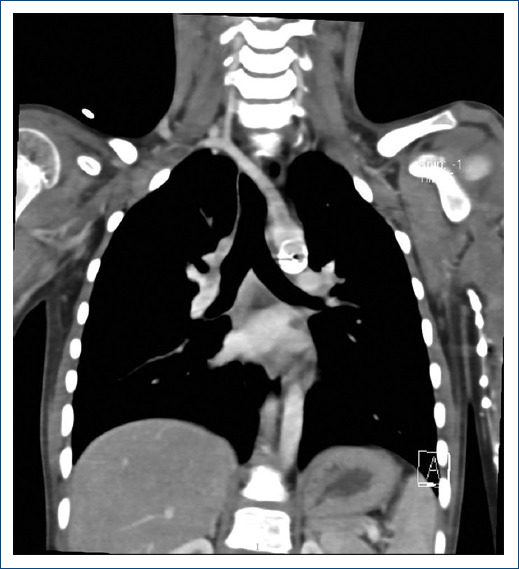

The lusoria artery has a prevalence of 0.5-2% in the general population. The abnormal development of the aortic arch forms vascular rings around the trachea and esophagus, causing pressure on them and leading to characteristic symptoms such as chest pain, difficulty breathing, and/or swallowing. Conventionally, only the subclavian artery was severed to release the esophagus, as done in neonates. However, this can lead to long-term hypotrophy of the thoracic limb. The surgical intervention remains controversial, with limitations, and it is only to be performed when the patient presents with symptoms. In the following two cases, a two-stage minimally invasive approach is described: first, a left lateral minithoracotomy for lusoria artery sectioning, and second, a supraclavicular approach for reimplantation into the right carotid artery.